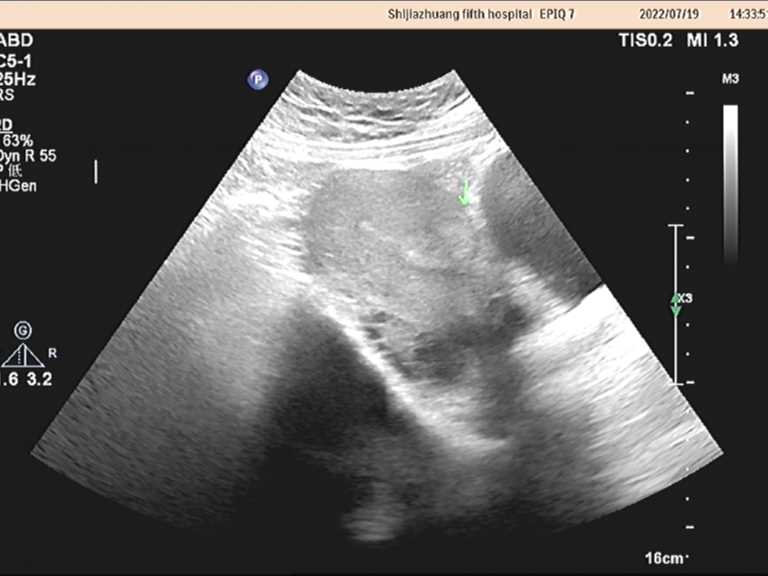

图3 子宫肌瘤消融术后15个月复查子宫形态恢复正常,子宫肌瘤几乎消失。